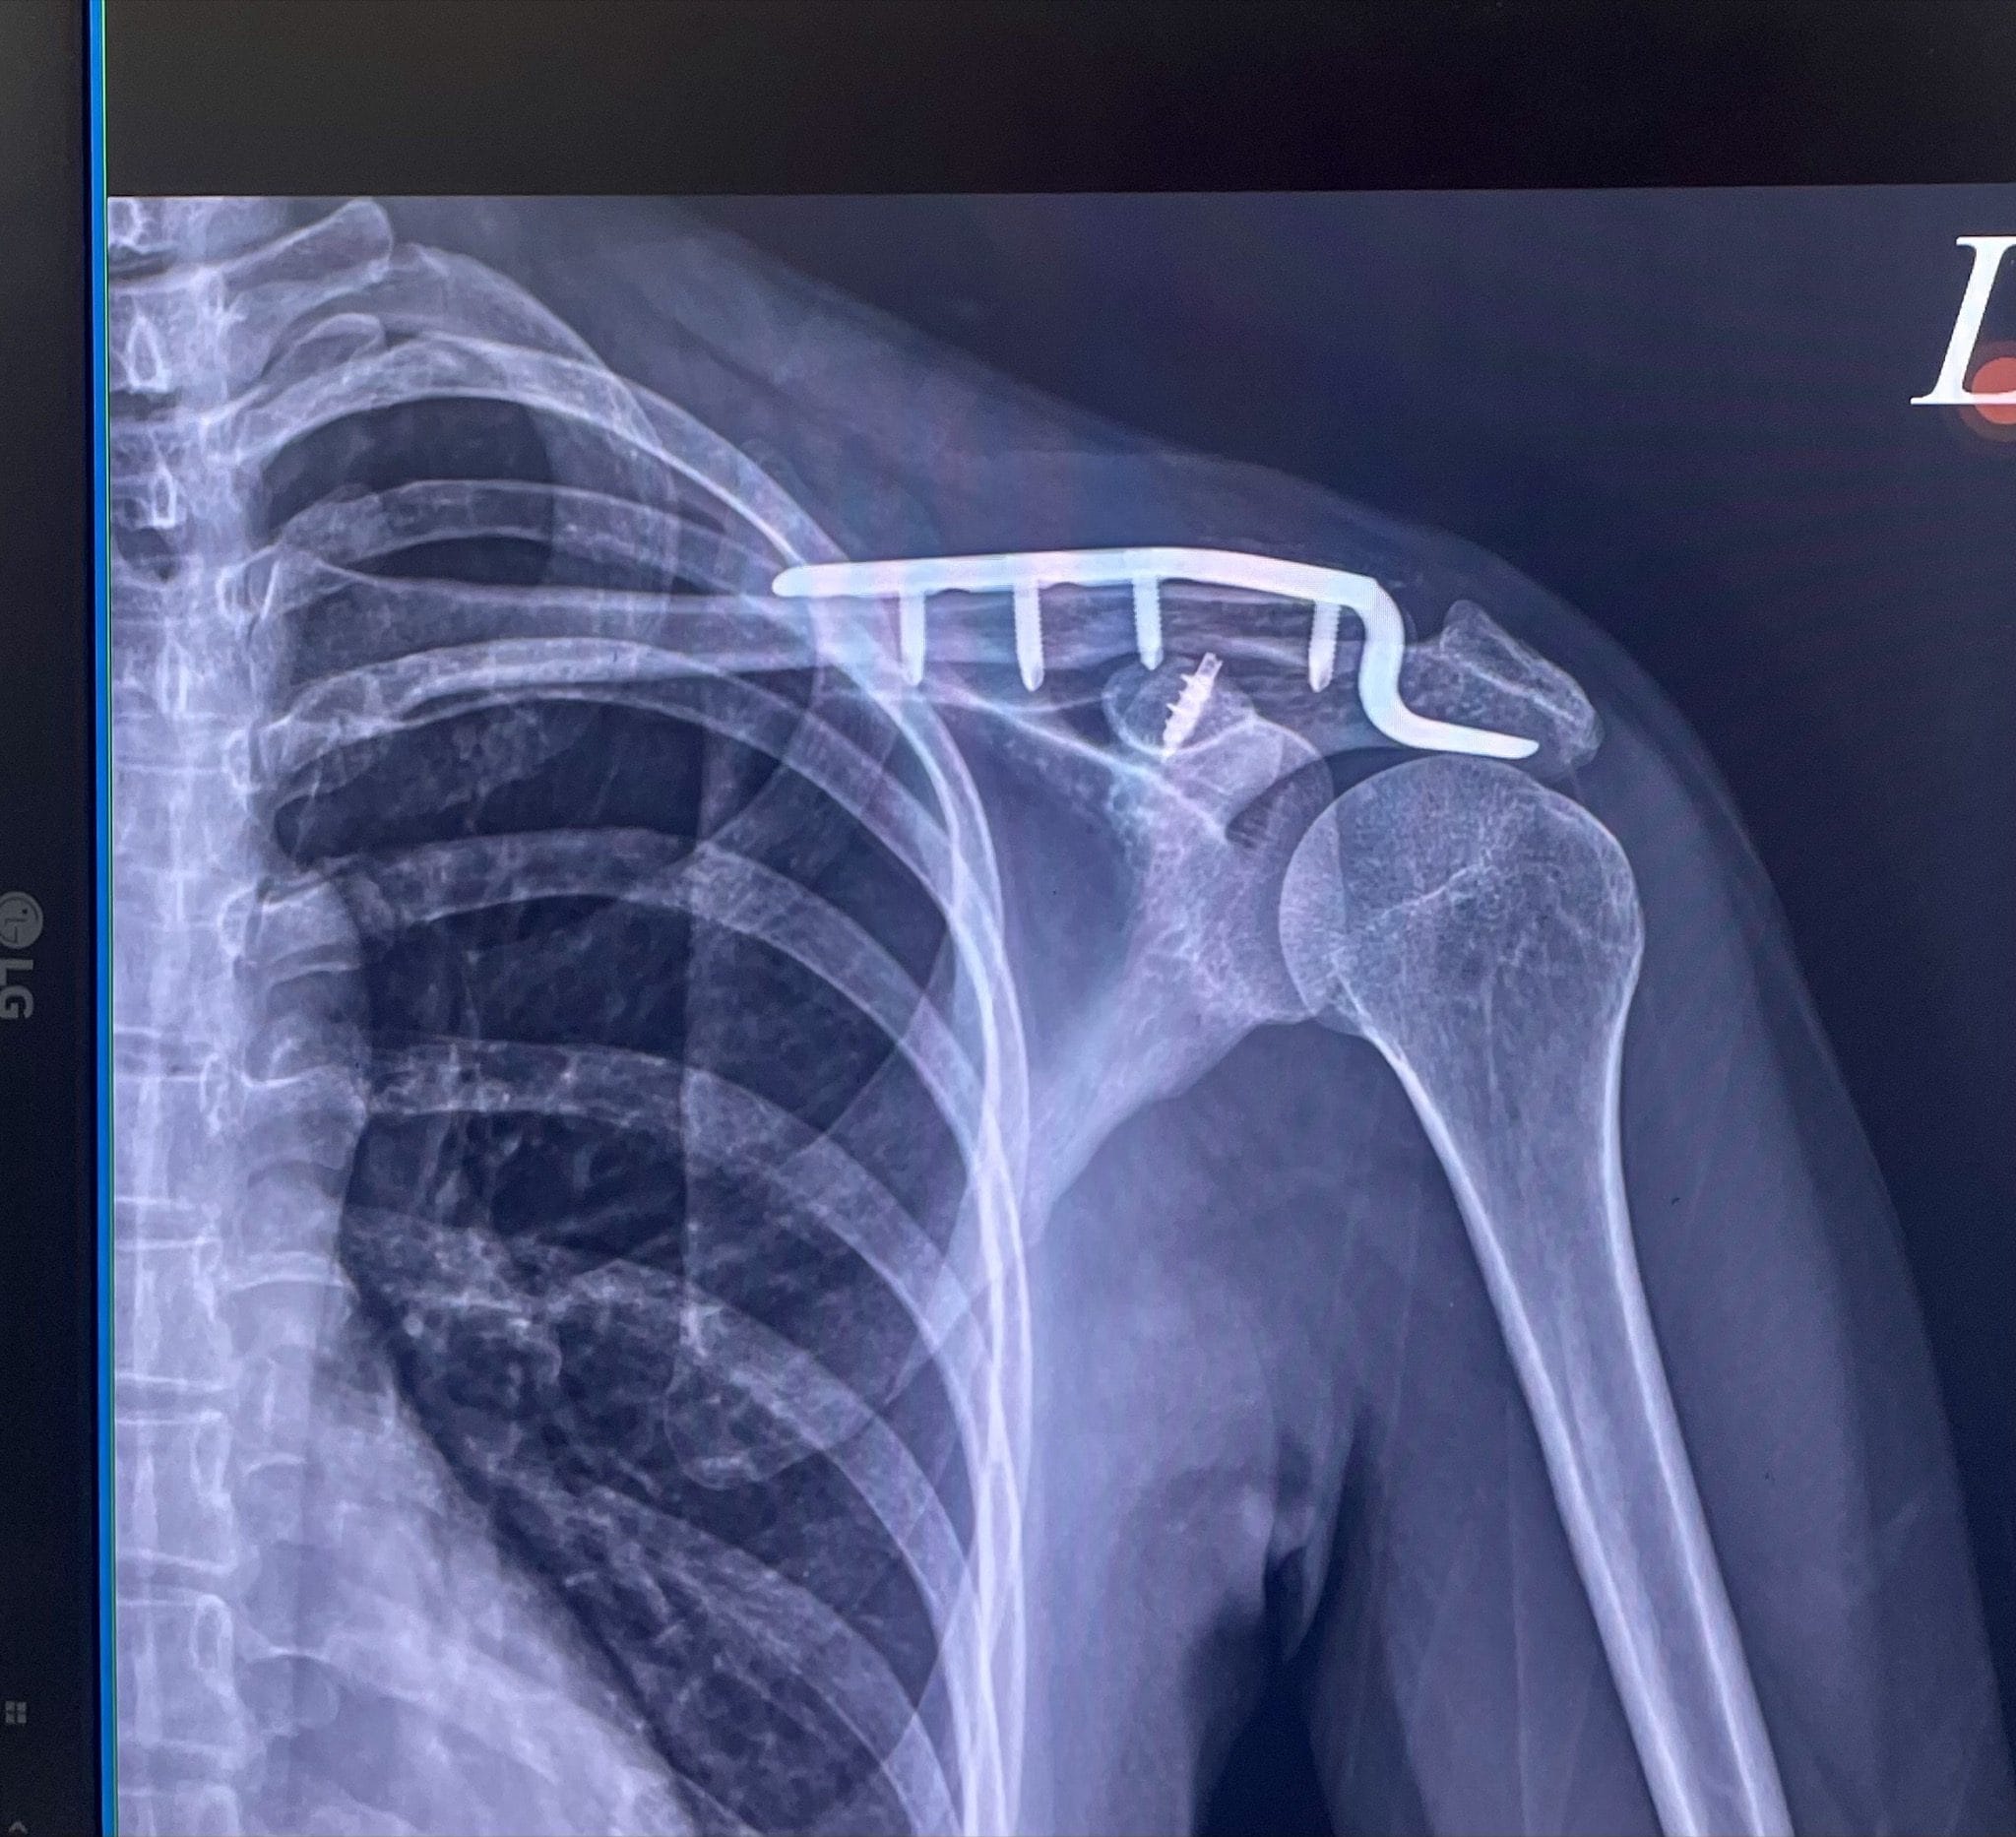

往下了解事件全貌 ↓民國 115 年 1 月 17 日,原告Doris參加東三塔自行車活動時,被告翁先生從後方切入車道,未保持安全距離,後輪撞上原告前輪,導致原告摔車,造成左側鎖骨骨折,緊急手術植入鈦金屬骨板,醫囑恢復需一年以上。

左側遠端鎖骨位移性骨折,手術植入鈦金屬骨板,恢復需一年以上

被告僅付 $27,000 後即拒絕履行 — 不及體內鈦金屬骨板費用 $124,668 的四分之一。

東三塔自行車挑戰活動,台2線 32.3K。原告左側鎖骨骨折,緊急手術植入鈦骨板。